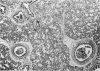

Images in this article